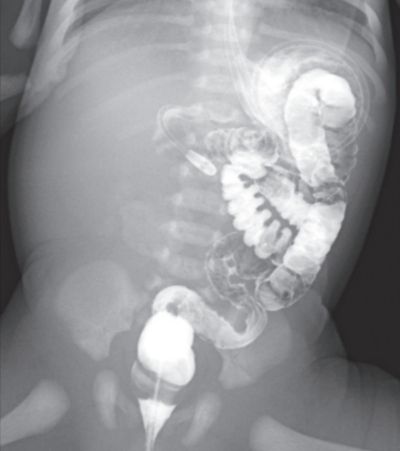

血液所見:赤血球 560 万、Hb 18.5 g/dL、Ht 48 %、白血球 11,000、血小板 18 万、PT-INR 1.0(基準 0.9~1.1)、APTT 30 秒(基準対照32.2)。血液生化学所見:総蛋白 6.8 g/dL、アルブミン 4.0 g/dL、AST 40 U/L、ALT 10 U/L、クレアチニン 0.5 mg/dL、Na 135 mEq/L、K 4.0 mEq/L、Cl 98 mEq/L、尿素窒素 7.0 mg/dL。CRP 0.1 mg/dL。上部消化管造影検査で十二指腸より先に造影剤が通過しなかった。注腸造影像と腹部超音波像(カラードプラ)を別に示す。